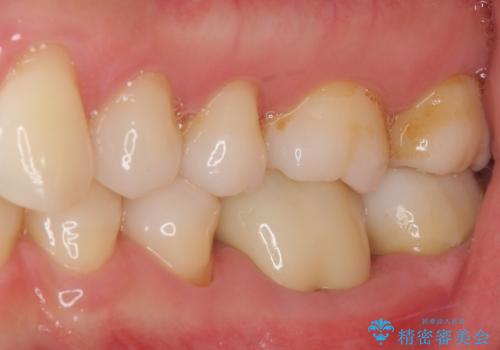

根管治療を終えた後には、今まで気になっていた痛みが消え、快適に日常生活を送れるようになりました。

痛みが取れるとともに、気になっていた大きな銀歯も自然なセラミックとなり、患者様には大変満足していただけました。